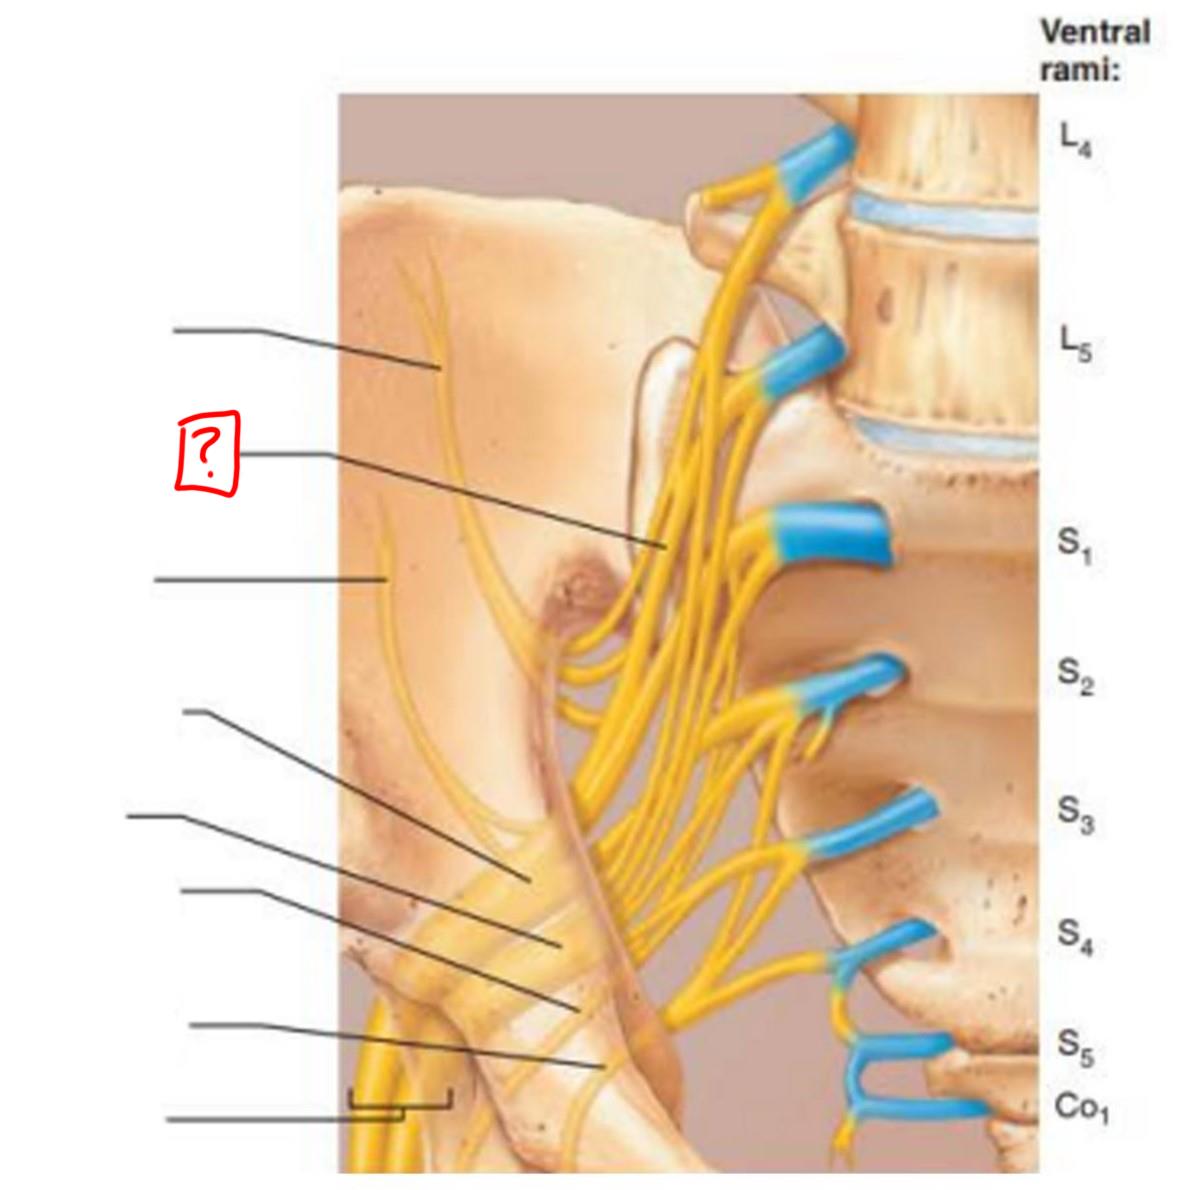

sacral plexus

L5-S4

superior gluteal

inferior gluteal

pudendal

sciatic

posterior femoral cutaneous

superior gluteal

lumbosacral trunk

inferior gluteal

common fibular

tibial

posterior femoral cutaneous